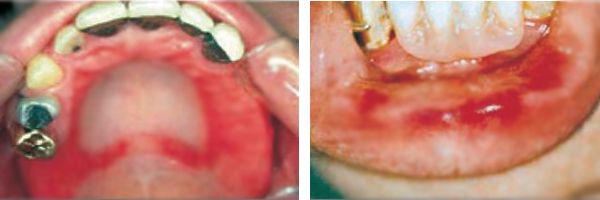

U zdrowej osoby błona śluzowa jamy ustnej jest jasnoróżowa, gładka i błyszcząca, bez oznak stanu zapalnego ani obrzęku.

W przypadku alergii na protezy zębowe błona śluzowa reaguje podrażnieniem, a u pacjenta mogą wystąpić następujące objawy:

Podczas badania dentysta ocenia stan błony śluzowej jamy ustnej, zwracając uwagę na zaczerwienienie, obrzęk, nadżerki, wysypkę, pęknięcia, suchość, strupki, pienistą ślinę i inne objawy podrażnienia.